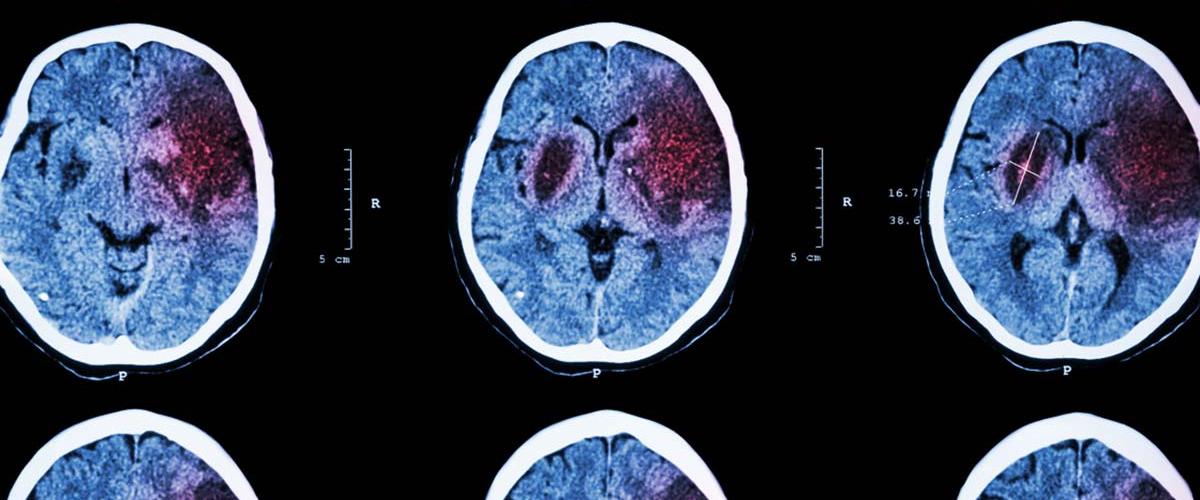

Исследователи из Лундского университета (Швеция) определили вариант гена MAP3K6, который может вызывать патологии мелких сосудов головного мозга и инсульт. В настоящее время основными факторами риска инсульта считается образ жизни и наличие сопутствующих сердечно-сосудистых заболеваний, однако новая работа подтверждает результаты предыдущих исследований о важной роли генетики в природе возникновения болезни.

Команда наблюдала за 15 взрослыми людьми, которые принадлежали к одной семье. Восемь из них перенесли инсульт. После изучения образцов тканей и генетического скрининга ученые обнаружили, что все 8 пациентов являются носителями одинаковой мутации MAP3K6, а также также увидели схожие изменения в кровеносных сосудах.